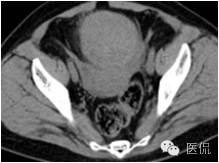

◆为单发肿瘤,表现为盆腔内实性肿块,囊性区较小;境界较清楚;肿瘤体积一般较大

◆CT表现:平扫呈等或稍低密度肿块,低于子宫肌层,可伴少量低密度囊变区,无壁结节

◆增强肿瘤实性成分呈轻-中度不均匀延迟强化,明显弱于子宫肌层;也可无强化